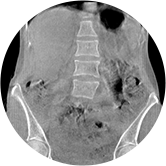

• 腰椎

三维脊柱应用

• 全身姿态评估

WR-3D能提供一种负重位状态下全身的姿态和三维空间任一平面平衡评估,使全脊柱术后评价更客观、真实 。通过各种临床参数包括骨盆、脊柱参数评价骨盆、脊柱平衡,避免由于髋膝屈曲造成的代偿性脊柱失衡的发生,WR-3D提供了三维空间任一平面平衡评估测量方法,可以更加定量地评估手术效果 。